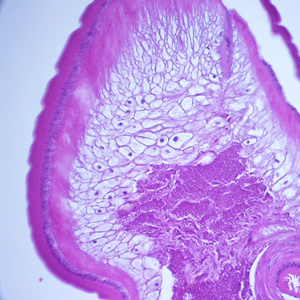

A 36-year-old immigrant from Mozambique presented to his health care provider with heartburn and chronic right abdominal pain. All previous ova and parasite (O&P) examinations were negative. An endoscopy was performed, upon which a worm-like object was observed in the ascending colon near the ileocecum. The suspicious object, measuring approximately 7 mm in length, was removed, collected in 10% formalin, and sent to Pathology for work-up. The object was sectioned, stained with hematoxylin and eosin (H&E) and reviewed by the attending pathologist, who in turn captured the following images and sent them to DPDx for telediagnosis assistance. What is your diagnosis? Based on what criteria?

Figure A